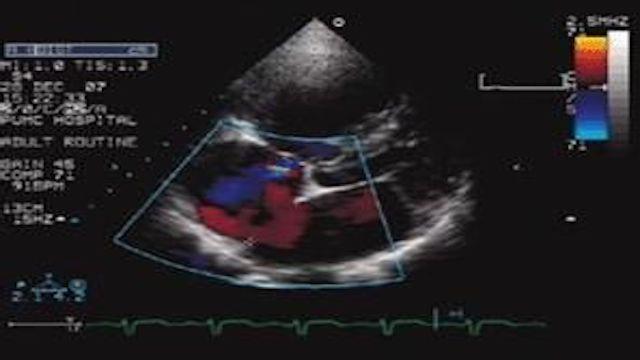

5、心臓超音波検査:心臓超音波検査は、心臓の筋肉と検査の内部解剖学を見て、それは直接冠状動脈を見ることはできませんが、心筋虚血や壊死がある場合、それは間接的に心臓の血液供給の状況に対応するように、心筋の動きに影響を与えます;

7.心エコー検査心臓の構造と機能を見る非侵襲的な検査です。これは心臓の構造と機能を見る非侵襲的な検査です。 虚血か梗塞かは心室壁の動きや厚さなどを見ることで判断します。虚血の場合、心室壁の動きは弱くなり、協調性がなくなり、梗塞した心筋は薄くなり、あるいは動かない(収縮しない)、あるいは逆に動く(収縮する)ようになり、医学的には「心室壁腫瘍」と呼ばれ、「付着壁血栓」ができることもある。大きな梗塞のある患者では、超音波で測定した心機能が低下することがある。

心臓超音波検査は、心臓の大きさ、可動性、収縮力を測定する定規のようなものである。

- 心臓超音波は音波の原理に基づいている。心臓から反射された音波を受信し、心臓超音波検査装置で画像に変換することで、心臓の個々の心房と心室の大きさ、心臓の収縮力、弁の状態、心臓の活動を直接測定することができる。しかし、心臓超音波検査では通常、冠動脈の狭窄や閉塞を直接見ることはできない。

- より軽症の心筋虚血や冠動脈疾患では、通常、心臓の大きさの変化、心臓の収縮力の変化、心臓の活動の変化はみられない。したがって、心臓超音波検査が正常または基本的に正常であることを示唆しても、心筋虚血や冠動脈疾患がないことの証明にはならない。

- 重度の心筋虚血冠動脈疾患、あるいは比較的大きな心筋梗塞は、心臓超音波検査で心収縮力の変化としてはっきりと確認することができる。心筋活動の変化、さらには心臓弁の機能異常も見られる。このようにして、心筋が重度の虚血に陥っていることが間接的に推測できる。

5.心臓超音波

心臓超音波検査は心臓の構造の変化を反映するもので、心臓の収縮・拡張機能が正常かどうか、駆出率が正常かどうかに加えて、心房や心室の壁の破損や肥厚の有無、心房や心室の肥大の有無、心臓の弁の狭窄や閉鎖不全の有無などを反映することができます。

5.超音波検査と血管内超音波検査:心臓超音波検査は、心臓の心室壁の動き、左心室の機能と形態を調べることができ、この方法は現在最も一般的に使用されている検査手段の一つである。乳頭筋機能、心破裂、腔内血栓、心室壁腫瘍などの診断に重要な価値を持つ。血管内超音波検査は、冠動脈内の狭窄の程度や壁の形態を明らかにすることができ、これは有望な新技術である。